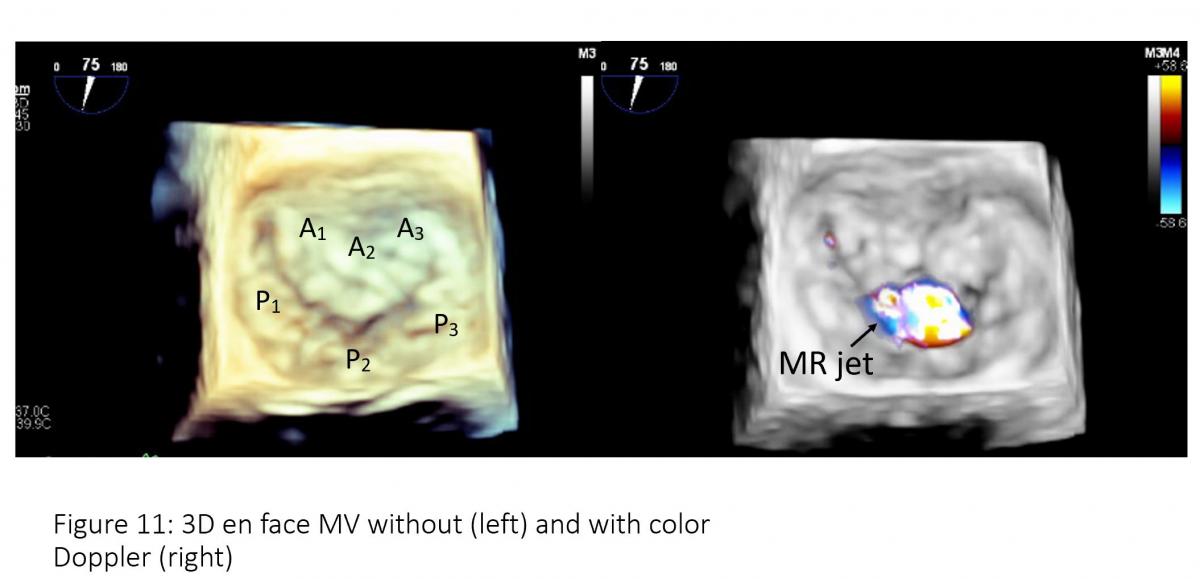

Figure 11: 3D enface mitral valve (left) and 3-D enface mitral valve with color Doppler flow mapping (right). Note: Mosaic color on the central of A2/P2 which is regurgitant jet location.

To facilitate the communication, both echocardiographer and implanter should be familiar with essential TEE imaging views during mitral clips (Figures 6-8). For transseptal guidance, bicaval TEE view and short-axis basal heart (aortic valve) view are commonly used and often in a XPlane/biplane view (Figure 9). For device advancement guidance in the LA to mitral valve oblique 45 degree view of left pulmonary vein, left atrial appendage/coumardin ridge is often used (Figure 9). For mitral valve, 4-chamber (Figure 7), commissure 2-chamber view (Figures 7-8), LVOT long-axis or 3-chamber view (Figures 7-8) are most commonly used. Off axis 2-chamber views (Figures 7-8) and off-axis LVOT views (Figures 7-8) are used to see P1/A1 and P3/A3 segments of mitral valve. 3D TEE of en face mitral valve view with and without color Doppler flow mapping (Figure 10) is used to guide positioning clip system and clip arm alignment.

• enface views of the mitral valve, thus facilitating further assessment of mitral valve morphology and pathology, and location of the lesion, measurement of mitral valve area, measurement of 3D color MR jet vena contracta which can be helpful for further determination of severity of MR which is important for patient selection.